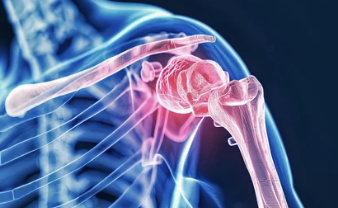

쇄골은 우리 몸에서 상체를 연결하는 중요한 뼈로, 어깨와 가슴을 이어주는 역할을 해요. 그러나 위치상 외부 충격에 취약해 쉽게 골절이 발생할 수 있어요.

- 증상: 쇄골 골절이 발생하면 어깨와 목 부위에 심한 통증이 생기고, 팔을 움직이기 힘들어져요. 골절 부위가 붓거나 멍이 들기도 하고, 뼈가 비정상적으로 튀어나온 것처럼 보일 수 있어요.